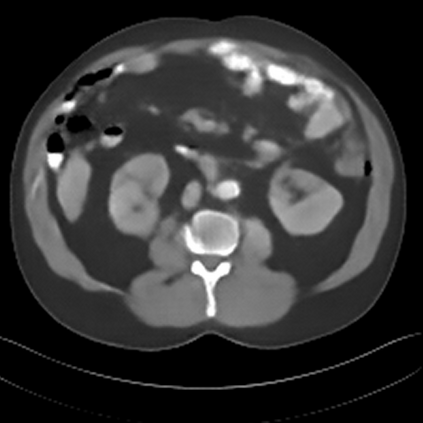

Sparse-view computed tomography (CT) -- using a small number of projections for tomographic reconstruction -- enables much lower radiation dose to patients and accelerated data acquisition. The reconstructed images, however, suffer from strong artifacts, greatly limiting their diagnostic value. Current trends for sparse-view CT turn to the raw data for better information recovery. The resultant dual-domain methods, nonetheless, suffer from secondary artifacts, especially in ultra-sparse view scenarios, and their generalization to other scanners/protocols is greatly limited. A crucial question arises: have the image post-processing methods reached the limit? Our answer is not yet. In this paper, we stick to image post-processing methods due to great flexibility and propose global representation (GloRe) distillation framework for sparse-view CT, termed GloReDi. First, we propose to learn GloRe with Fourier convolution, so each element in GloRe has an image-wide receptive field. Second, unlike methods that only use the full-view images for supervision, we propose to distill GloRe from intermediate-view reconstructed images that are readily available but not explored in previous literature. The success of GloRe distillation is attributed to two key components: representation directional distillation to align the GloRe directions, and band-pass-specific contrastive distillation to gain clinically important details. Extensive experiments demonstrate the superiority of the proposed GloReDi over the state-of-the-art methods, including dual-domain ones. The source code is available at https://github.com/longzilicart/GloReDi.